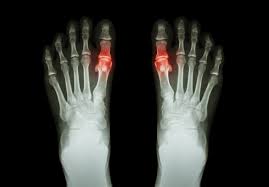

Chụp xquang ổ khớp để kiểm tra mức độ tổn thương của sụn, đĩa đệm quanh khớp

Bệnh gout thực chất chính là bệnh do rối loạn chuyển hóa nhân purin, thuộc nhóm bệnh rối loạn chuyển hóa mà ra. Cụ thể khi bị rối loạn chuyển hóa purin sẽ khiến cho hàm lượng acid uric bị gia tăng mạnh, thận không kịp bài tiết hết ra ngoài, từ đó sẽ hình thành các tinh thể muối urat tại khớp xương cũng như các bộ phận khác trong cơ thể, là nguyên nhân dẫn tới bệnh gout. Bệnh thường khởi phát đột ngột với cơn đau đầu tiên ở ngón chân cái rồi lan sang các khớp lân cận, kèm theo đó là hiện tượng sưng tấy và nóng khớp.

Siêu âm ổ khớp bị đau và nghi ngờ bị gout để chuẩn đoán chính xác giai đoạn của bệnh